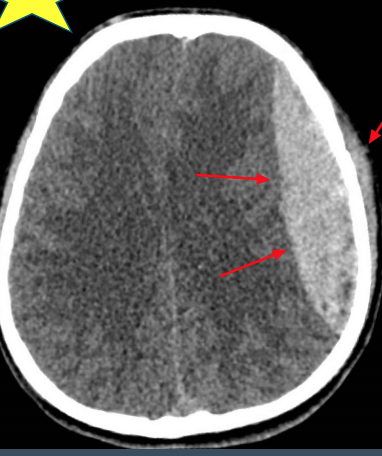

What type of injury is shown in the provided image?

Epidural hemorrhage (convex/lens shaped)

lucid interval - then pass out

YES - surgery is indicated